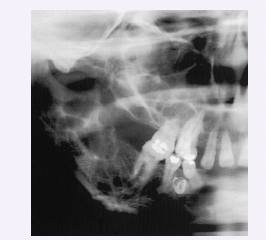

Cherubism

● Genetic disorder that typically appears between ages 2 – 5, with progression during childhood and

stabilization or regression after puberty

● Multilocular, bilateral, radiolucent (“soap bubble”) lesions in the mandible and sometimes the maxilla

● Jaw expansion leads to facial swelling and can cause tooth displacement, malocclusion, and delayed

eruption of teeth

● Lesions are histologically identical to those of a central giant cell granuloma